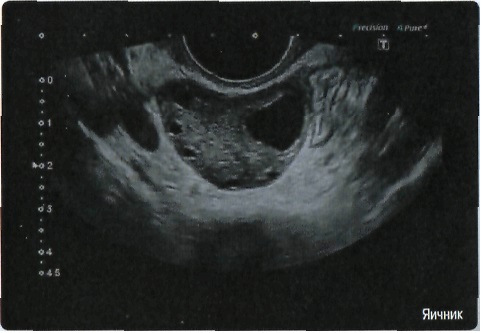

• ApliPure - технология повышения качества изображения

• Precision Imaging - технология получения изображений мелких деталей с четко очерченными границами и высокой однородностью

Общая визуализация, Гинекология и акушерство, УЗИ для кардиологии

Общая визуализация:

Да

Гинекология: